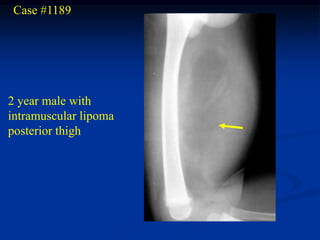

Case #1189 2 yearmale with intramuscular lipoma posterior thigh

• 64.